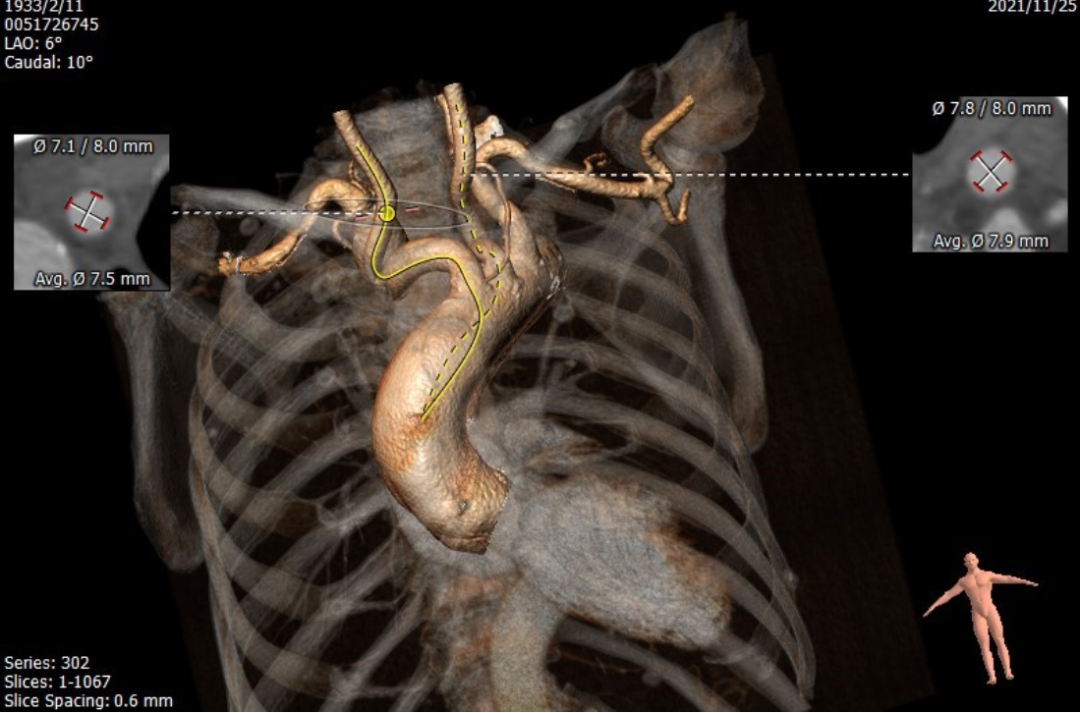

术前CT评估:

Annulus 22.8*27.8mm Perimeter=78.4mm

SOV 34.6*34.9*36.4mm

STJ 37.7*38.7mm

LVOT 23.3*28.6mm Perimeter=83.8mm

Ascending Aorta 38.7*39.8mm

左冠高度15.1mm

右冠高度22.8mm

经股动脉入路评估

右锁骨下动脉

颈动脉

该病例特点为:该患者考虑为心脏联合瓣膜病导致心力衰竭,并且药物治疗效果差,有瓣膜手术的指征。患者88岁高龄,BMI 17.3Kg/m2,营养状况差,合并肾功能不全,STS评分20.848%,外科手术风险极大,考虑患者心脏瓣膜疾病以主动脉瓣为主,二尖瓣及三尖瓣关闭不全为继发性改变,建议首先行TAVR治疗。该患者行TAVR治疗需要面临以下几个方面的问题:1、TAVR术中应用造影剂会导致患者肾功能恶化,由于患者心功能差,术前水化很有可能会加重心衰。2、患者股动脉、髂动脉扭曲,特别是主动脉极度迂曲,经股动脉入路可能出现器械通过困难,或者器械被血管夹持的情况。该患者双侧颈动脉及右侧锁骨下动脉扭曲严重,左侧腋动脉是可选择入路,但是可能面临缝合效果欠佳无法压迫止血,外科切开止血的情况。3、患者为三叶瓣,无钙化,瓣叶对人工瓣膜的锚定力不足,给术中瓣膜定位、释放带来了很大挑战,另外有术后瓣膜移位的风险。4、该患者主动脉瓣病变以反流为主,选择人工瓣膜型号oversize要偏大,导致房室传导阻滞发生率高,需要延长留置临时起搏电极的时间,但是患者三尖瓣重度关闭不全,很有可能导致临时起搏电极脱位,导致灾难性的后果;另外,长时间留置临时起搏电极,导致患者行动不便,增加了卧床相关并发症的发生率。

沿Super stiff导丝将65cm长22F鞘管(GORE DRYSEAL FLEX)缓慢送至升主动脉(视频2)。将6FAL2.0造影导管送至升主动脉,导丝跨瓣成功后,将塑形好的Lunderquist导丝送至左心室内,送入VitaFlow 30mm瓣膜(视频3)。精准定位瓣膜位置(视频4),在180次/分起搏下释放瓣膜(视频5),将输送系统及鞘管同步缓慢回撤至降主动脉,回收并撤出输送系统(视频6)。主动脉根部造影显示瓣膜形态良好,轻度瓣周漏(视频7)。瓣膜释放后,心电监护提示三度房室传导阻滞,穿刺右侧锁骨下静脉,送入主动电极并固定于室间隔右室侧,体外固定并连接脉冲发生器,程控起搏频率为70次/分,起搏稳定(视频8)。应用ProGlide缝合右股动脉穿刺部位。术后患者即刻苏醒,安全返回普通病房。

3、 该患者经下肢入路血管严重扭曲,65cm的GORE DRYSEAL FLEX鞘管为此类患者提供了解决之道。

4、 为获得良好的输送效果,鞘管头端已经跨越过主动脉弓部至升主动脉,在此过程中需要特别谨慎操作,而且为了减少导丝对动脉壁的损伤,未选用Lunderquist导丝,而是选用相对较软的Super stiff导丝。